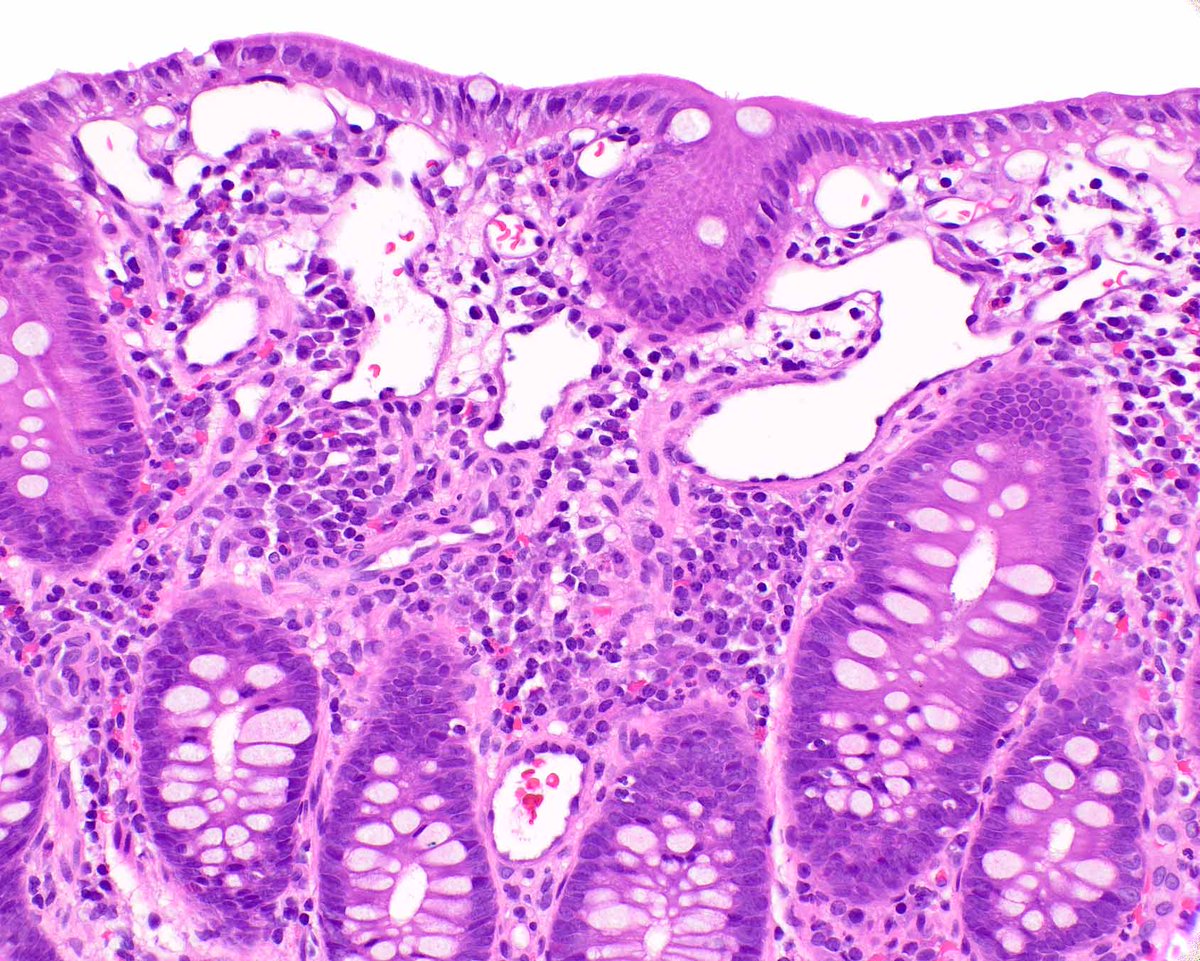

This is a striking example of portal hypertensive colopathy in a patient with cirrhosis. #umiamipath